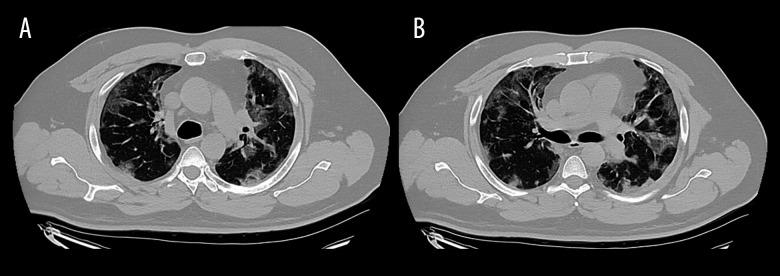

BACKGROUND This report presents the case of a 49-year-old man with pulmonary aspergilloma 6 months after hospitalization and mechanical ventilation for COVID-19 who was treated with robot-assisted lobectomy. COVID-19-associated pulmonary aspergillosis is a life-threatening complication of SARS-CoV-2 infection. Aspergilloma, a delayed complication of COVID-19, is rare. Major risk factors for pulmonary aspergilloma include neutropenia, solid organ transplantation, prolonged high-dose corticosteroid therapy, hematological malignancy, cytotoxic therapy, acquired immunodeficiency syndrome, and chronic granulomatous disease. Common symptoms include cough, shortness of breath, fatigue, wheezing, weight loss, fever, and chest pain. Hemoptysis is the most severe complication of pulmonary aspergilloma. Treatment options include antifungals, bronchial artery embolization, and surgery. Surgical treatment is considered definitive for patients who do not respond to antifungal medications. CASE REPORT We describe the case of a 49-year-old man with pulmonary aspergilloma who developed a delayed sequela of SARS-CoV-2 infection. He presented to a pulmonary clinic 6 months after a severe COVID-19-related hospitalization, with symptoms of mild hemoptysis, cough, and shortness of breath. A computed tomography scan of the chest revealed a right upper lobe cavitary lesion approximately 9.6×6.1 cm in size. Bronchoalveolar lavage during bronchoscopy revealed Aspergillus fumigatus. The patient did not respond to antifungal treatment and was successfully treated with a robotic-assisted lobectomy. CONCLUSIONS Aspergillus infection should be considered in COVID-19 survivors with pulmonary symptoms. Minimally invasive robotic lobectomy is a feasible option for high-risk patients with post-COVID-19 aspergilloma and hemoptysis who are resistant to medical treatment.

背景 本报告介绍了一名49岁男性的病例,该患者在因新冠肺炎住院并接受机械通气6个月后发生肺曲菌球,接受了机器人辅助肺叶切除术治疗。新型冠状病毒肺炎相关肺曲霉病是严重急性呼吸综合征冠状病毒2感染的一种危及生命的并发症。肺曲菌球作为新冠肺炎的一种迟发性并发症较为罕见。肺曲菌球的主要危险因素包括中性粒细胞减少、实体器官移植、长期大剂量皮质类固醇治疗、血液系统恶性肿瘤、细胞毒性治疗、获得性免疫缺陷综合征和慢性肉芽肿病。常见症状包括咳嗽、气短、乏力、喘息、体重减轻、发热和胸痛。咯血是肺曲菌球最严重的并发症。治疗选择包括抗真菌药物、支气管动脉栓塞和手术。对于对抗真菌药物无反应的患者,手术治疗被认为是确定性的治疗方法。病例报告 我们描述了一名患有肺曲菌球的49岁男性病例,这是严重急性呼吸综合征冠状病毒2感染的迟发性后遗症。他在因新冠肺炎严重住院6个月后到肺部门诊就诊,有轻度咯血、咳嗽和气短症状。胸部计算机断层扫描显示右肺上叶有空洞性病变,大小约为9.6×6.1厘米。支气管镜检查期间的支气管肺泡灌洗显示有烟曲霉。该患者对抗真菌治疗无反应,通过机器人辅助肺叶切除术成功治愈。结论 对于有肺部症状的新冠肺炎康复者应考虑曲霉菌感染。对于对药物治疗耐药的新冠肺炎后肺曲菌球合并咯血的高危患者,微创机器人肺叶切除术是一种可行的选择。